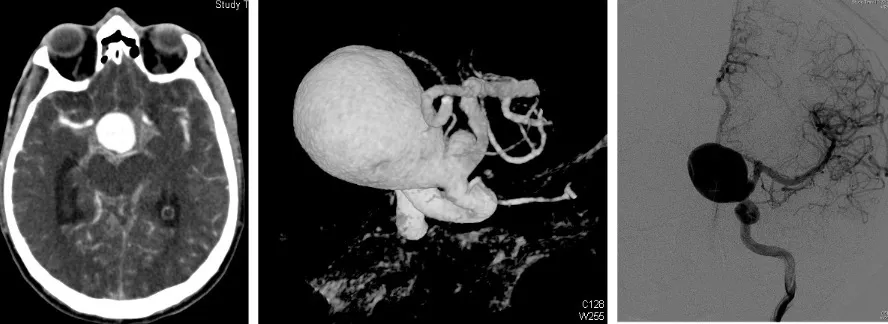

El diagnóstico de la hemorragia subaracnoidea y del aneurisma causante se realiza en dos fases complementarias:

En primer lugar, se confirma la presencia de sangre en el líquido cefalorraquídeo. La prueba fundamental es la tomografía computarizada (TAC), que permite visualizar la sangre en el espacio subaracnoideo. Cuando existen dudas diagnósticas —por ejemplo, para diferenciarlo de una meningitis—, puede realizarse una punción lumbar que confirme la presencia de sangre en el LCR.

Una vez confirmada la hemorragia, es necesario identificar el aneurisma responsable. Para ello se emplean la angio-TAC (TAC con contraste vascular) y el estudio angiográfico cerebral (arteriografía), que no solo permiten localizar y caracterizar el aneurisma antes de la intervención, sino que también sirven para comprobar que el aneurisma se ha cerrado correctamente tras el tratamiento.

Un aneurisma cerebral es una dilatación de la luz arterial, es decir, un ensanchamiento anormal en la pared de una arteria del cerebro. En el ámbito cerebral, los aneurismas adoptan fundamentalmente dos formas:

- Saculares: son los más frecuentes (más del 90% de los aneurismas cerebrales). Se desarrollan en forma de saco que va creciendo progresivamente a partir de un punto débil de la pared arterial.

- Aneurisma gigante como masa expansiva: en casos excepcionales, el aneurisma alcanza un tamaño tan grande que se comporta como un tumor, comprimiendo las estructuras cerebrales vecinas y produciendo daño por efecto de masa.